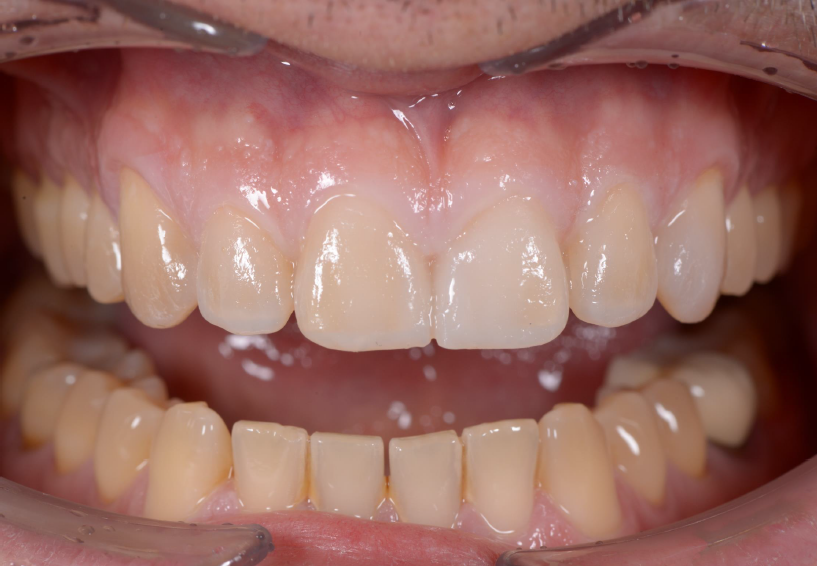

Close-up of teeth

Initial situation in the static occlusion.